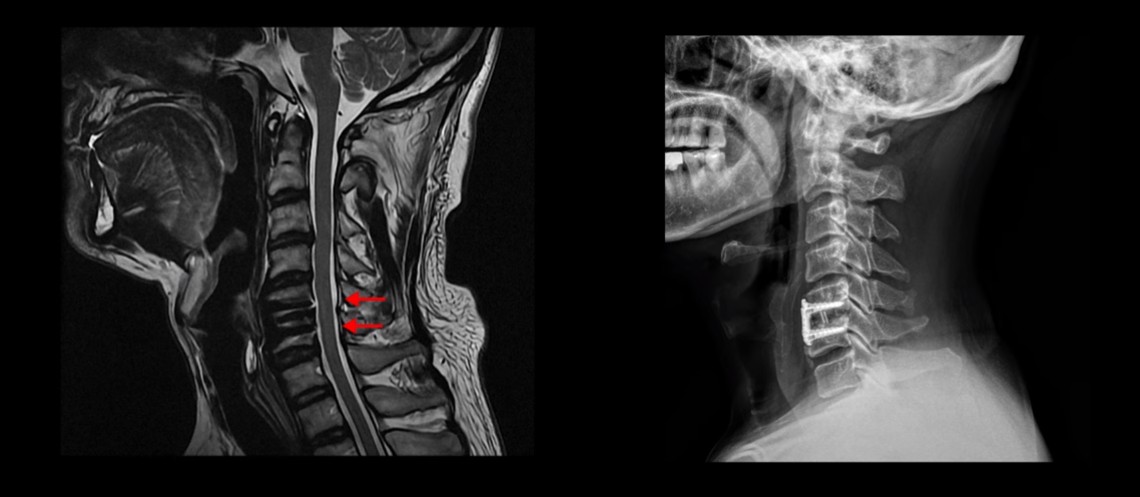

MRI를 보시면 목 5번 6번 마디에 나사가 박힌 유합술이 되어있습니다.

제자리에 나사가 잘 박혀 있고 유합술은 크게 문제가 없는 것으로 보입니다.

저희 모커리한방병원에서는 목이든 허리든 수술이 잘 됐다는 데도 계속 아프다면 당연히 근육 문제를 의심하고 치료해야 한다고 그렇게 반복해서 설명하는데도 신경 주사만 맞거나 아니면 치료를 포기하거나 아니면 추가적인 수술을 받는 분들도 있습니다. 이 환자분도 보시다시피 목의 다른 마디에도 퇴행성디스크와 협착이 있습니다.

이분도 X-ray를 보면 완전한 일자목, 거북목 환자입니다.